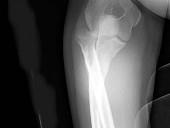

问题 女,55岁,跌倒后右手痛,结合X线平片表现,正确的诊断是?(?)

选项 A.柯莱斯骨折 B.蒙泰贾骨折 C.加莱阿齐骨折 D.尺桡骨骨折 E.反柯莱阿齐骨折

答案 B